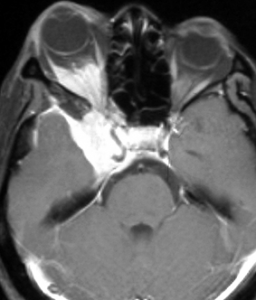

典型的な髄膜腫

この髄膜腫は中程度の大きさのものです。円蓋部髄膜種という最も多い最も手術の簡単なタイプです。麻痺や失語症やてんかんなどの症状はありません。とても美しくて若い女性の髄膜腫でしたが,子供に遺伝はしませんし,癌などと違ってタバコなどこれといった原因がなくて発生するものです。

MRIでの髄膜腫の見え方は撮影の仕方によっていろいろです。左からT1強調画像,T2強調画像,フレア画像といいます。腫瘍の横に小さく白い領域がありますが,これは脳の腫れた部分で脳浮腫といいます。髄膜腫があると周囲に脳浮腫が生じることがあります。

最も見やすいのが,ガドリニウム造影剤を注射して撮影するものです。一般的に髄膜腫は造影剤で白く映し出されます。この腫瘍は左脳側にあります。MRIの軸面という輪切りの写真では左右が逆になりますから注意してください。脳を下から見た図になっています。MRIはいろいろな方向から腫瘍を見ることができますが,右は冠状断という正面から見た図です。よく見ると腫瘍の上と下のはじっこに線状に糸を引いたように造影される部分があります。これをテールサイン(しっぽのサイン)といいます。腫瘍が硬膜に沿って延びている可能性があることを示しています。